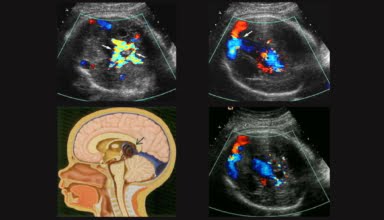

[Video] Siêu âm tầm soát tim thai, Bs Trọng

Siêu âm tầm soát tim thai là bài Bs Nguyễn Quang Trọng trình bày trong GE Workshop tại Bệnh viện đa khoa Kiên Giang, và đây cũng là bài giảng trong Khóa học Siêu âm Sản phụ khoa (BV Từ Dũ)

[Video] Siêu âm Doppler ứng dụng trong sản phụ khoa, Bs Trọng

Siêu âm Doppler ứng dụng trong sản phụ khoa là bài giảng trong Khóa học Siêu âm Sản phụ khoa (BV Từ Dũ) do Bs Nguyễn Quang Trọng giảng dạy.

[Video] Nguyên lý và kỹ thuật siêu âm Doppler, Bs Trọng

Nguyên lý và kỹ thuật siêu âm Doppler là bài giảng trong Khóa học Siêu âm Sản phụ khoa (BV Từ Dũ) do Bs Nguyễn Quang Trọng giảng dạy.